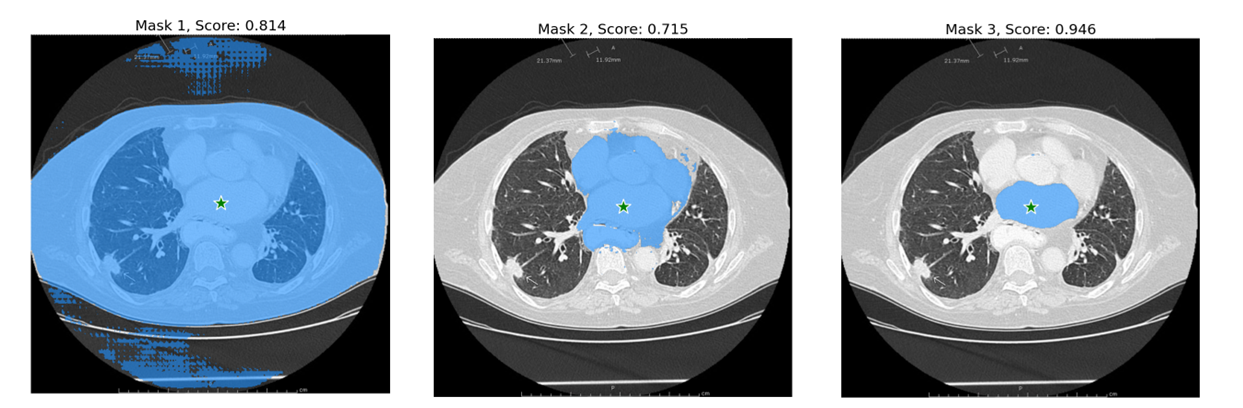

multimask_output=True (默认),SAM模型会输出3个分割目标和对应的置信度scores。这个设置主要是用于面对歧义的提示点,因为一个提示点可能在多个分割的目标内部,multimask_output=True 能够将包含该提示点的所有目标都分割出来。

如下面示例所示:2种车窗户、还有整个车均包含了五角星的提示点。

输出置信度不同的分割图:

for i, (mask, score) in enumerate(zip(masks, scores)):

plt.title(f"Mask {i+1}, Score: {score:.3f}", fontsize=18)